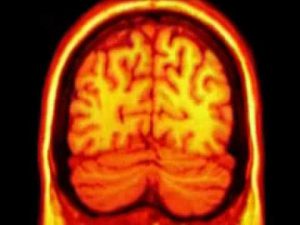

Enfermedades Cerebrales

Información sobre enfermedades cerebrales desarrollada por los profesionales especializados en neurorrehabilitación de Irenea, Instituto de Rehabilitación Neurológica de Vithas